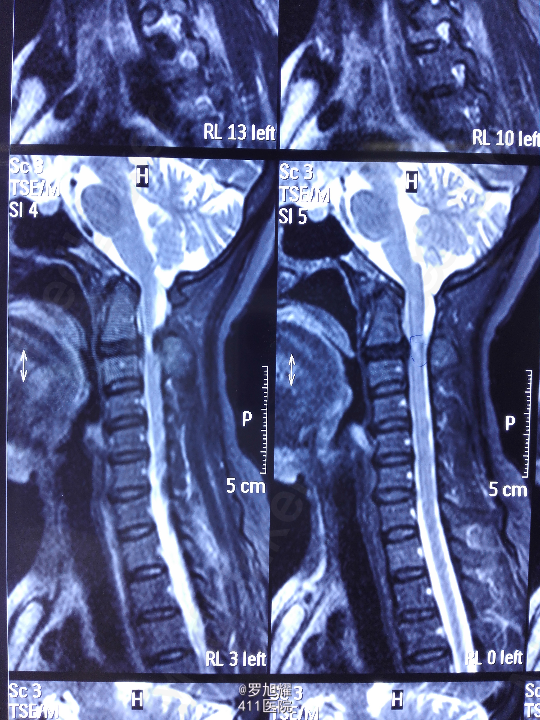

右侧躯体麻木1年,右上肢及下肢麻木2月余。 查体:颈椎活动受限,右上肢肘关节以远痛温觉减退,右侧胸4平面以下痛温觉及触觉减退,四肢肌力尚可,右侧霍夫曼征阳性,右侧上下肢所有腱反射亢进。 颈椎X线示:颈2椎板棘突缺如,颈3棘突肥大增高。 颈椎CT示:颈2椎板棘突缺如,颈3棘突肥大增高,颈2/3椎间盘突出,左侧颈2残留部分椎板进入椎管。枢椎齿突增生,寰枢关节退变。 颈椎MRI示:颈2/3椎间盘突出,左侧颈2椎板进入椎管,颈髓受压变性。

查体:颈椎活动受限,右上肢肘关节以远痛温觉减退,右侧胸4平面以下痛温觉及触觉减退,四肢肌力尚可,右侧霍夫曼征阳性,右侧上下肢所有腱反射亢进。 颈椎X线示:颈2椎板棘突缺如,颈3棘突肥大增高。 颈椎CT示:颈2椎板棘突缺如,颈3棘突肥大增高,颈2/3椎间盘突出,左侧颈2残留部分椎板进入椎管。枢椎齿突增生,寰枢关节退变。 颈椎MRI示:颈2/3椎间盘突出,左侧颈2椎板进入椎管,颈髓受压变性。